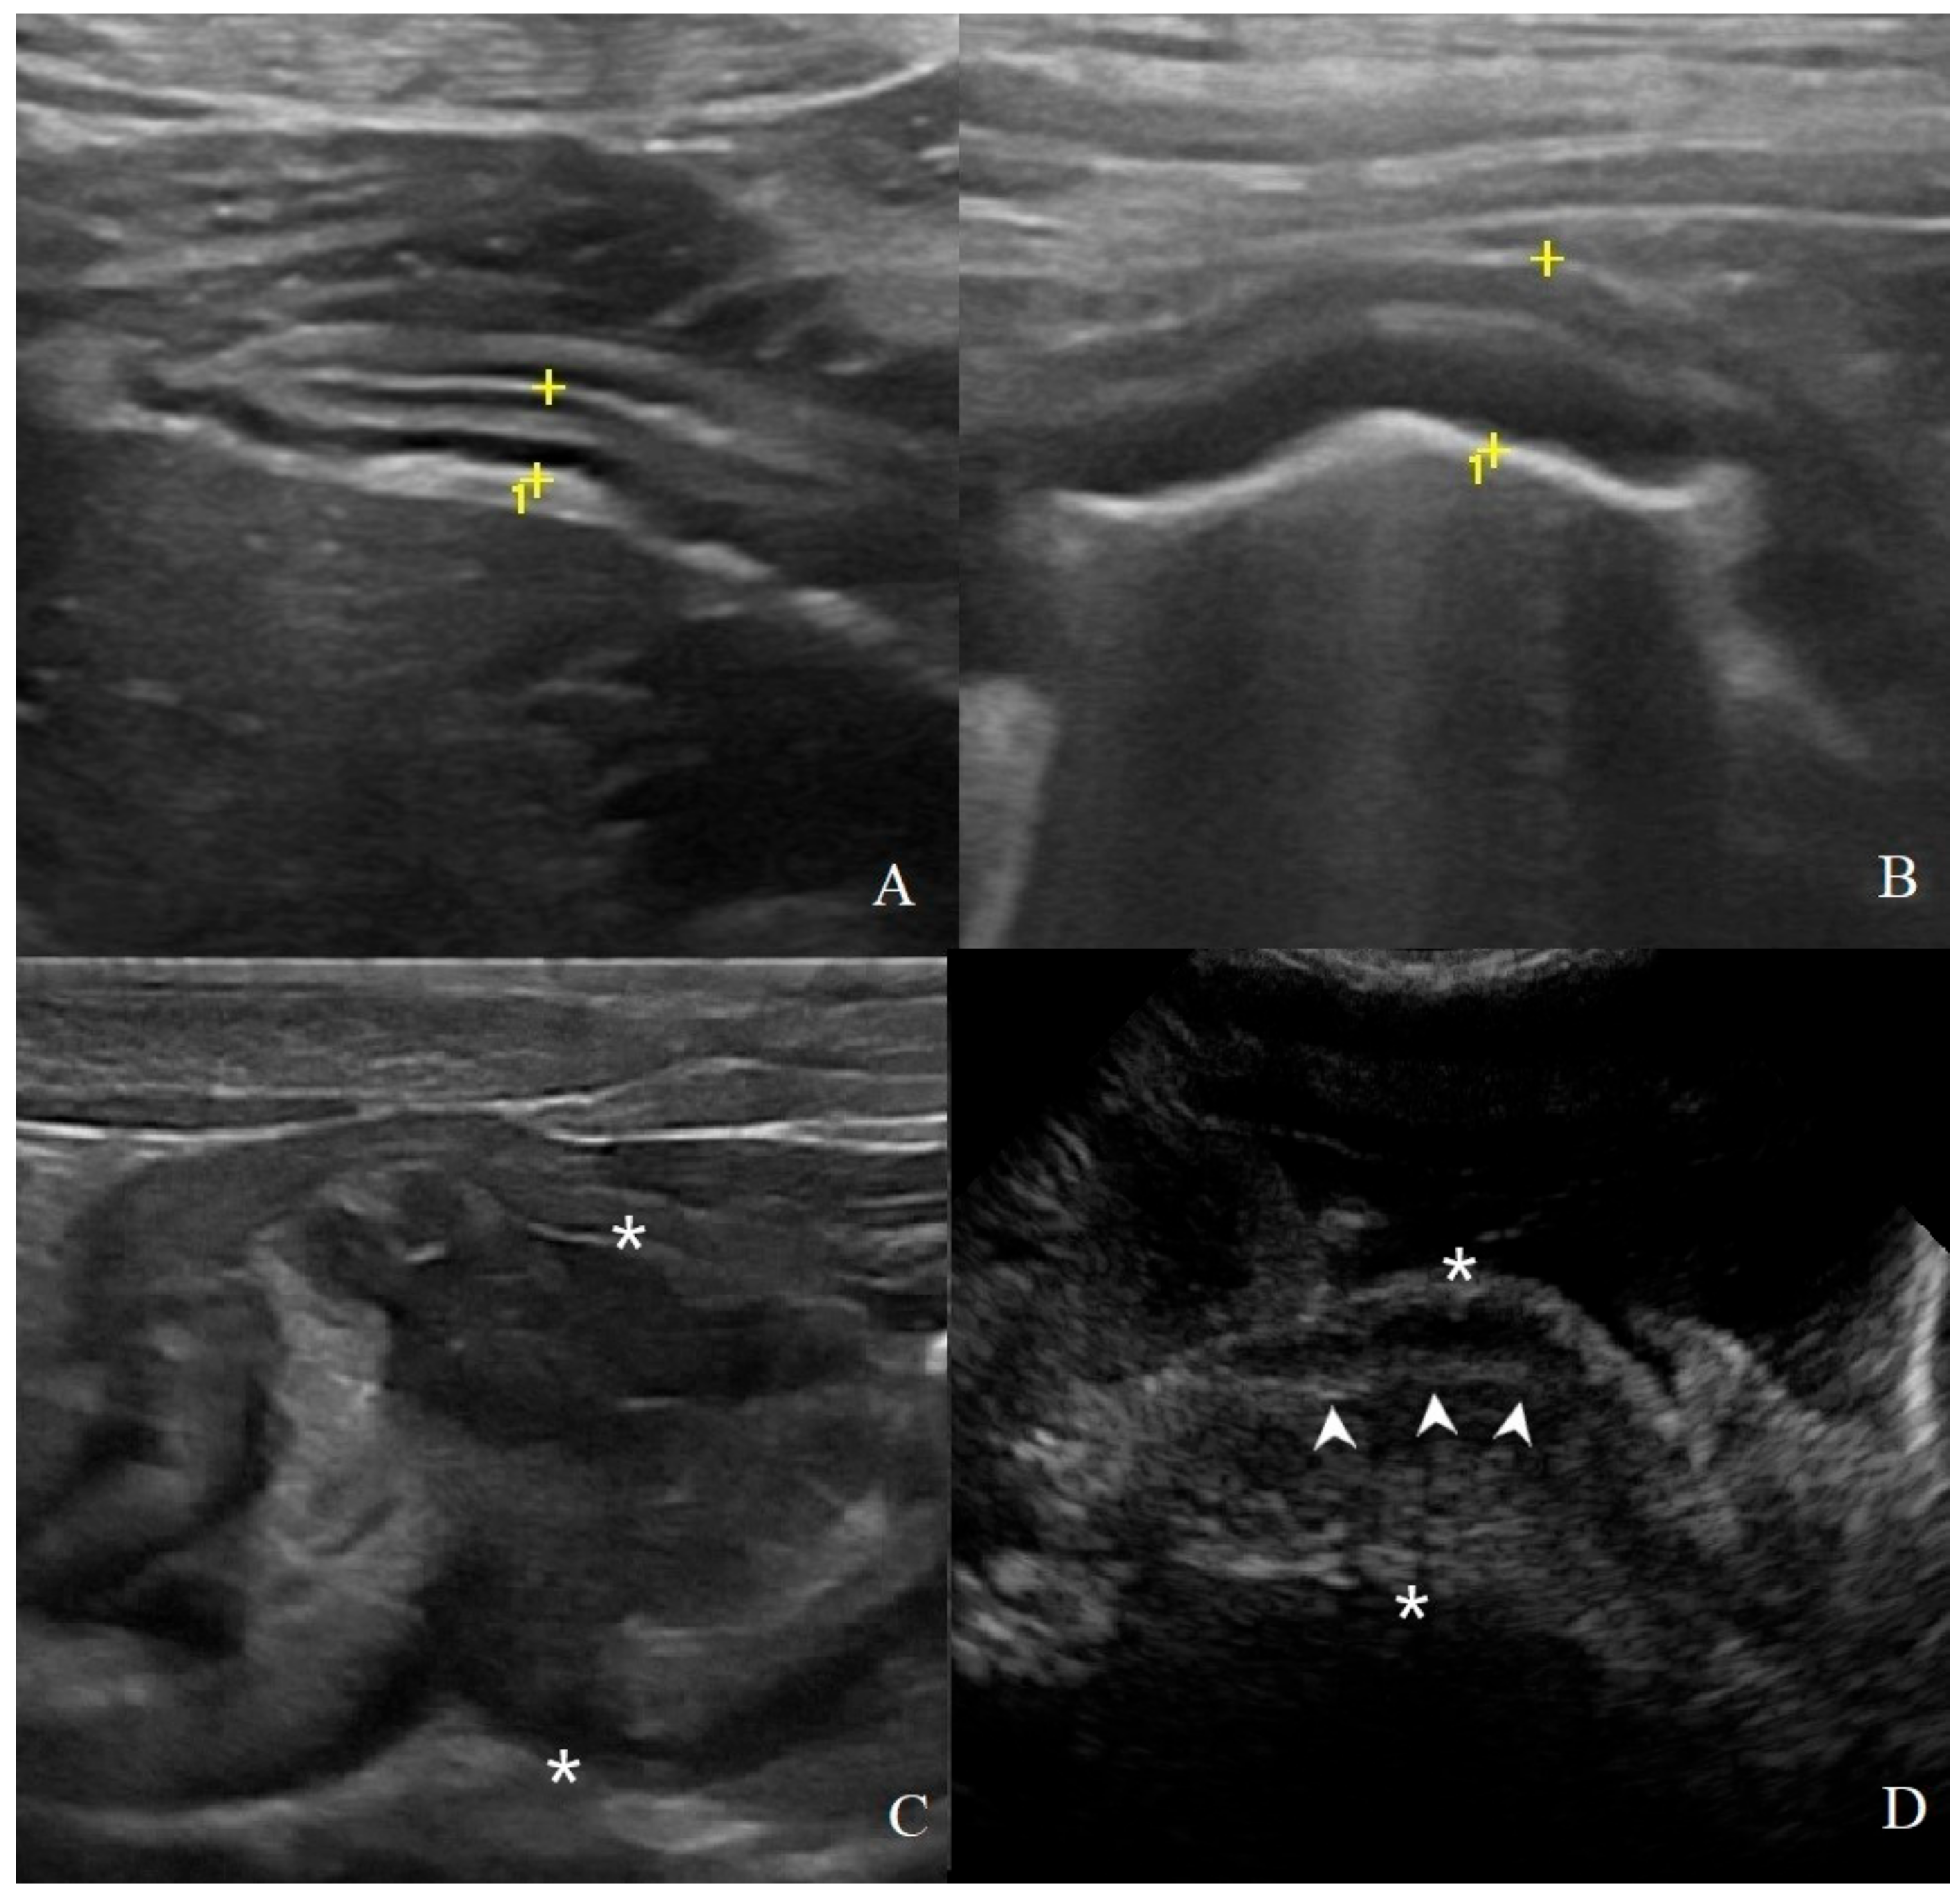

3.2. Analysis of B-Mode Examination

3.3. Analysis of CEUS Examination